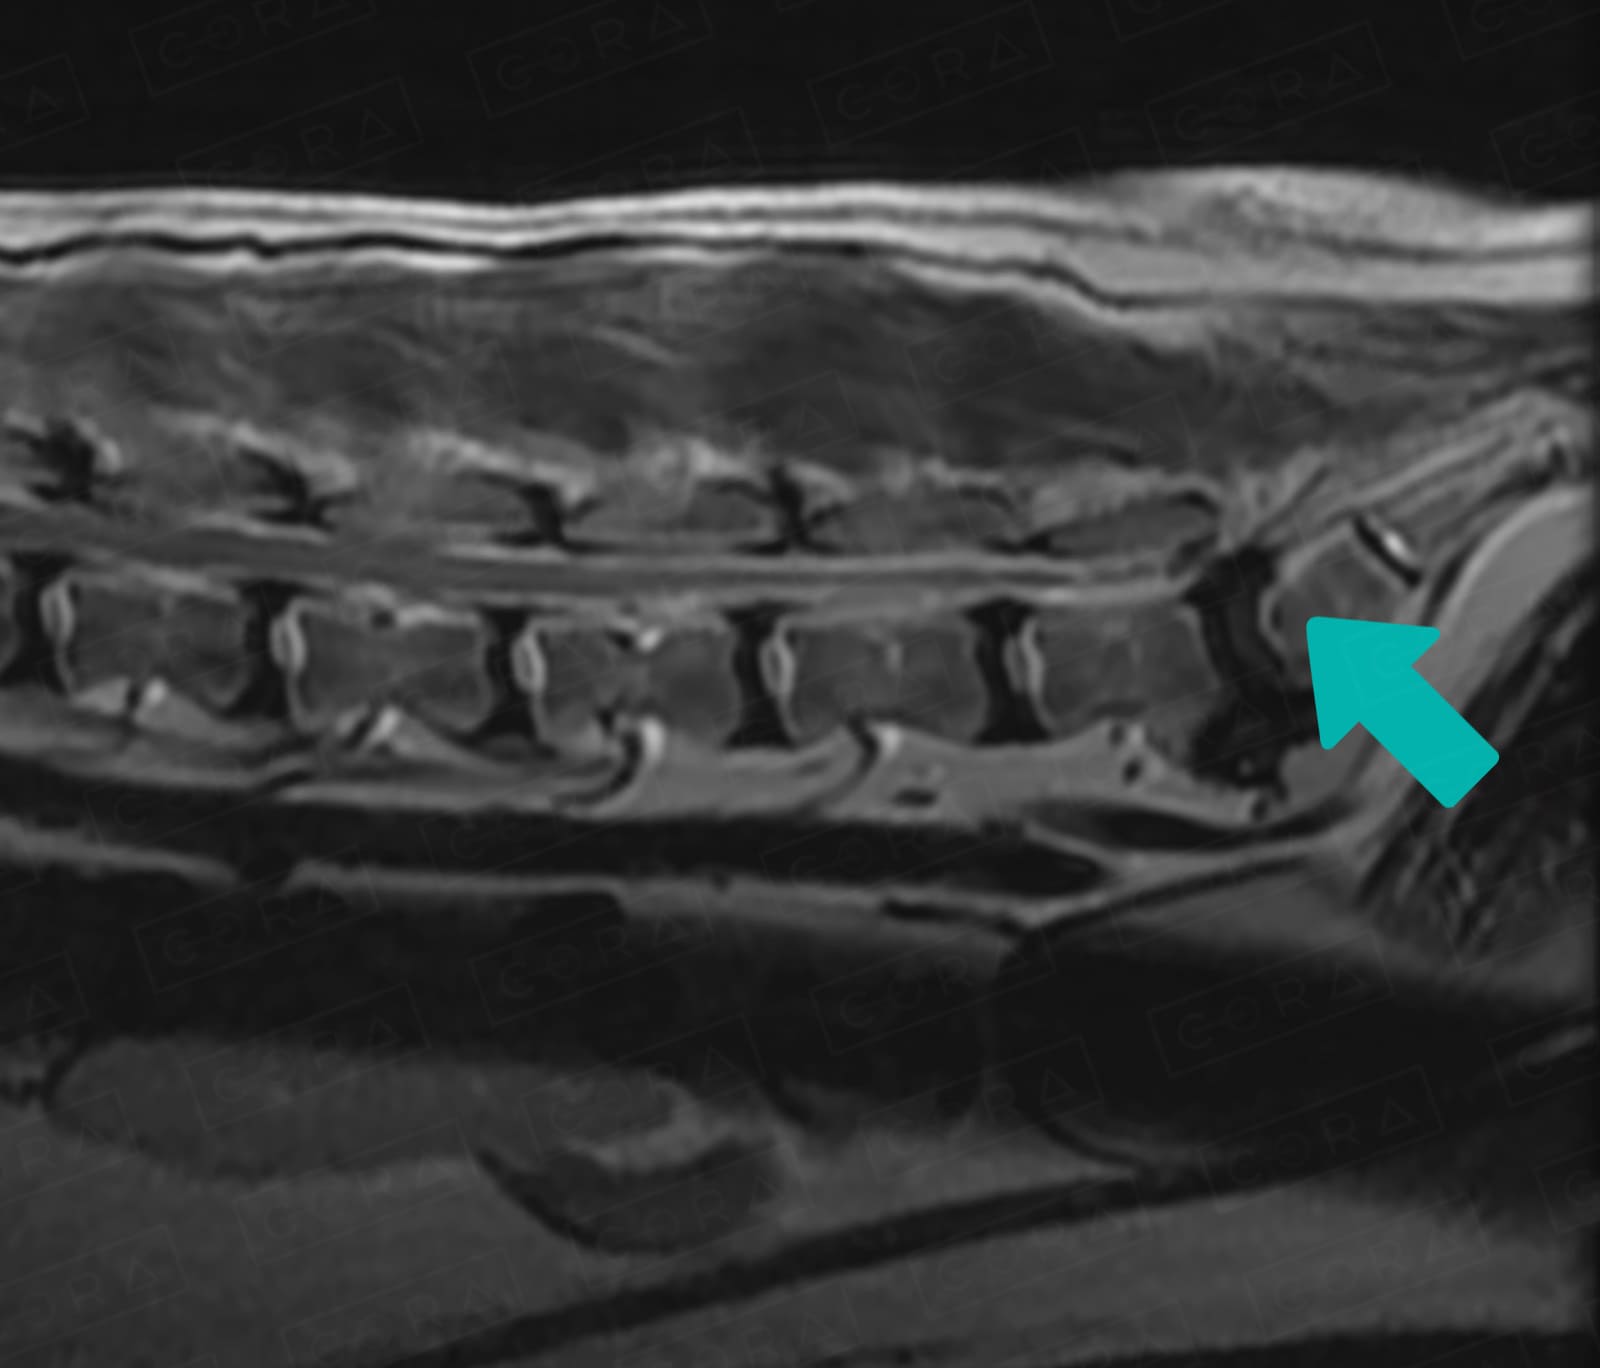

A síndrome da cauda equina refere-se a compressão das raízes nervosas da região lombossacra da coluna. Nessa porção final da medula a medula deixa de ser um tubo único e se ramifica em vários feixes nervosos.

Essa doença pode ser causada por hérnias de disco, tumores, fraturas e luxações, doenças degenerativas, infecção, entre outros:

Devido à instabilidade crônica, com frequência é notada uma espondilose ventral, popularmente conhecida como "bico de papagaio".